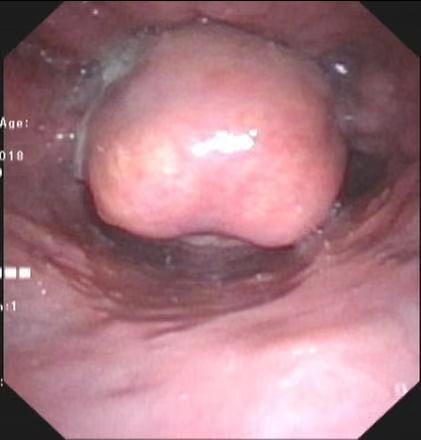

常德37岁的刘先生已咽痛3天,起初自认为是感冒,后来感觉咽痛症状逐渐加重,甚至吞咽不适,遂来湘雅常德医院耳鼻咽喉头颈外科门诊,在完善电子喉镜后,医生发现刘先生的会厌已肿胀如球,被考虑为急性会...